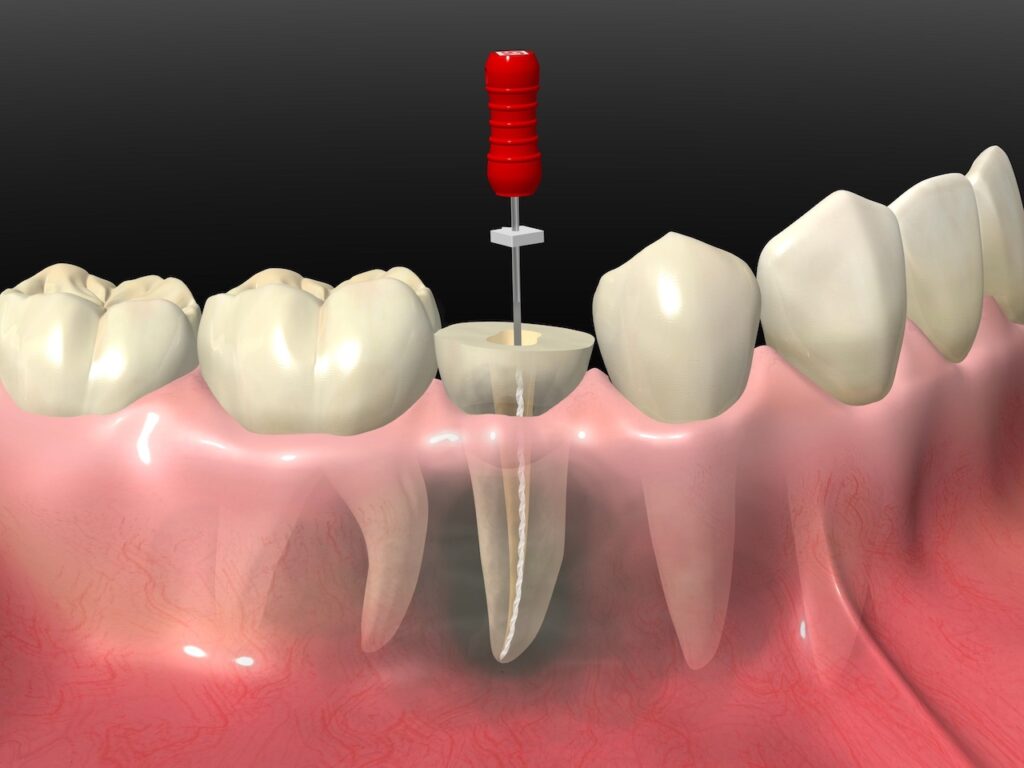

根管治療とは

根管治療とは、歯の中にある根管と呼ばれる細い管の中から、感染した神経や血管、汚染された組織を取り除き、内部をきれいに洗浄・消毒する治療法です。虫歯が進行して歯の神経まで達した場合や、過去に治療した歯が再び炎症を起こした場合に必要になります。

根管治療の目的は、歯を抜かずに残すことです。神経を取り除いた歯はもろくなりやすいため、最終的には被せ物などで補強しますが、天然歯をできるだけ残すことが長期的な口腔の健康には重要です。

根管は非常に細く複雑な構造をしており、肉眼での確認が難しいため、専門の器具やマイクロスコープなどを使用して慎重に治療を進めます。

根管治療の流れ

根管治療は、繊細で段階的な処置が必要な治療です。1回の通院で完了することはまれで、数回にわたって丁寧に進められます。各ステップには明確な目的があり、治療の成功率を高めるためには、患者さま自身も治療の流れを正しく理解し、通院を途中で中断しないことが大切です。

感染部位の除去と仮詰め

麻酔を行い、虫歯などで崩れた部分を削り、感染した神経や組織を除去します。根管内部を丁寧に洗浄・消毒した後、仮の詰め物をして密閉します。この処置は複数回にわたることが一般的で、毎回の洗浄と消毒が治療の成功を左右します。

根管内の充填

感染が完全に取り除かれたと判断された段階で、根管の内部に薬剤を詰めて密閉します。これにより、再感染を防ぎ、歯の内部を保護することができます。